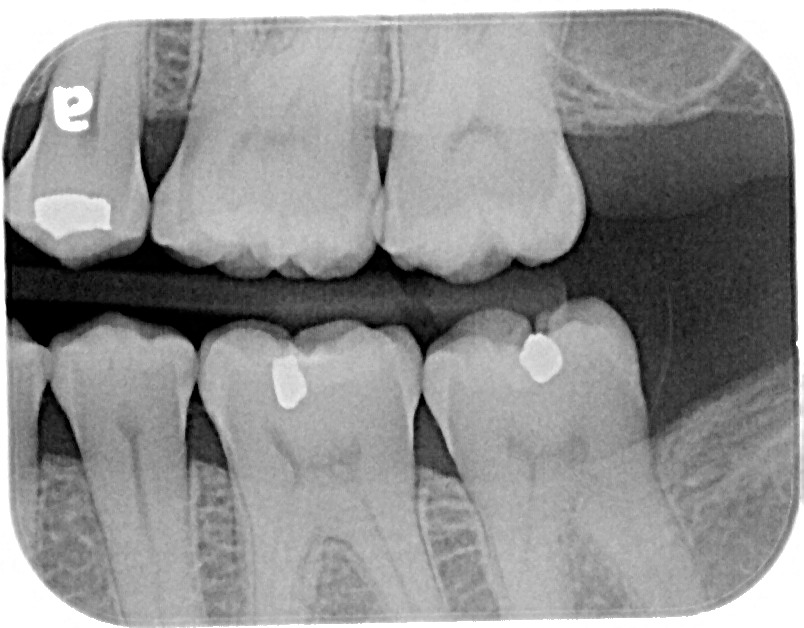

4) Or, my favorite, is apply to a marked segment of Superfloss and draw it through the contact area.

Figure 2

Figure 1

Figures 1 and 2 show his technique that he describes as the most effective method to getting the SDF directly on the interproximal surface.

Dr. Parrett and his patients like the results this treatment has provided. Additionally, he has not had any complaints of gum irritations when using this technique